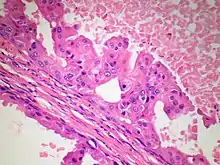

The microscopic histopathology of PACB tumors prepared with hematoxylin and eosin staining shows that >90% of the tumors consist of apocrine gland-like tissue. The lesions must also show that tumor cells have broken through their ducts of origin to invade adjacent tissue in at least one area. Most of the tumor cells (termed type A cells[15]) typically appear somewhat more irregular than normal apocrine gland cells. They have abundant eosinophilic (i.e. pink due to the uptake of the eosin dye) cytoplasm which contain numerous granules[11] and large mitochondria.[15] Their nuclei are large, variably sized and shaped, have multiple nucleoli (which are eosinophilic[11] and may be distinctively large in size[14]), and are surrounded by highly visible nuclear membranes. The cells are arranged into solid sheets, nests, papillae, and/or cords (see Figs. 1 and 2).[11] The tumor cells' cytoplasmic granules test positive when treated with the PAS diastase stain.[16] Binucleated cells, i.e. cells with two nuclei, are common.[10] Less commonly, type B apocrine cells are present; these cells have a more foamy and vacuolated cytoplasm (i.e. containing multiple vacuoles) than type A cells[15] and often resemble foamy histiocytes or sebaceous gland cells.[17] The tumor cells have low to moderate rates of proliferation based on their Ki-67 protein levels.[7] PACB tissues may have localized areas that contain mucin-like secretions within their luminal ducts,[10] localized areas of necrosis (i.e. foci containing dead or dying cells), and/or microcalcifications spotted throughout the apocrine tissue.[11] The stroma (i.e. connective tissue between the sheets, nests, papilla and cords of cells) typically contains non-malignant, infiltrating lymphocytes (see Fig. 3). In an examination of 41 PABC tumors, 33 (80.5%) had <50% of their stroma tissues infiltrated with these cells while 8 (19.5%) had ≥50% of their stroma tissues infiltrated with them. Tumors with ≥50% of their stroma infiltrated with lymphocytes tended to have carcinoma cells that had high rates of proliferation.[11] Metastatic and recurrent PACB tumors have a histopathology similar to their original primary tumors.[14]